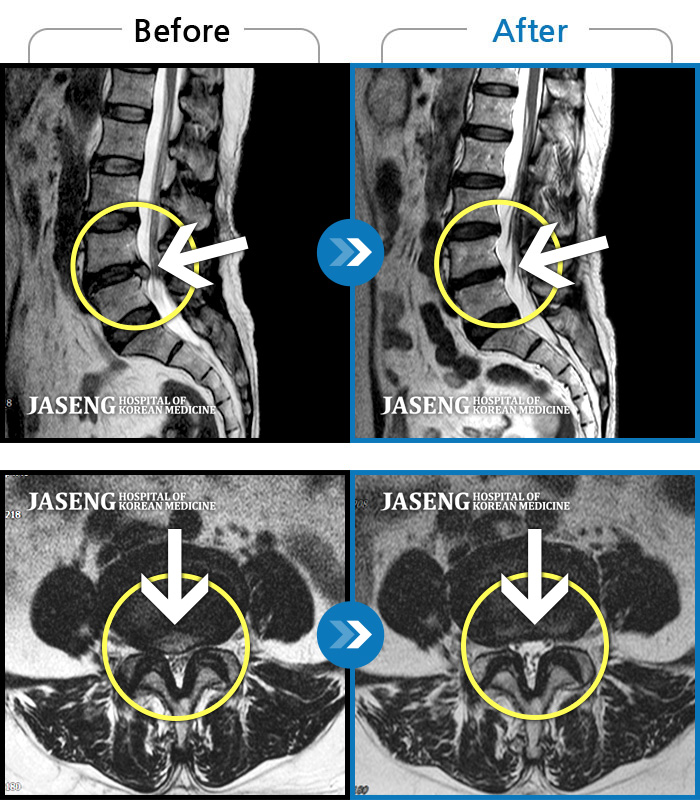

Before

After

환자에게 사전 동의를 받아 동일 조건에서 촬영되었습니다.

개인에 따라 치료 후 부작용이 발생할 수 있으니 의료진과 상담 후 치료를 진행하시기 바랍니다.

디스크가 터져 수핵이 흘러내려 우측 발등의 감각 저하와 엄지발가락 굴곡 근력까지 떨어져 있는 심각한 상태였습니다.